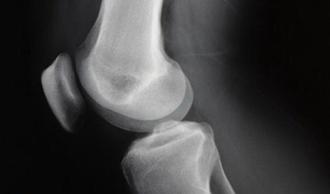

Luxación de rótula

luxación rótula